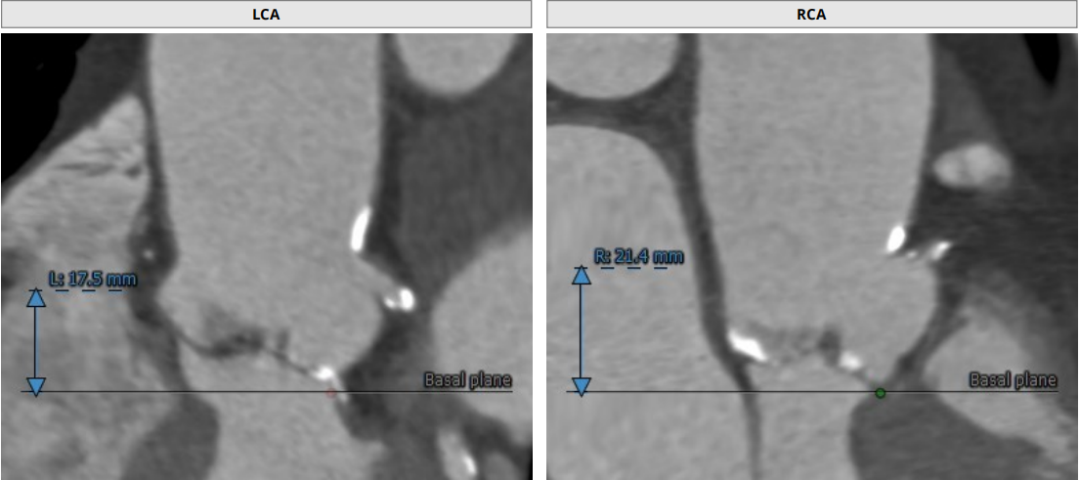

根部CT

三叶瓣,重度钙化,钙化主要分布在瓣叶游离缘,法式窦结构较大,双冠高度较高,升主动脉未见明显扩张,心脏角度40°,左室大小可,心肌肥厚,主动脉弓部走行较平缓,主动脉弓部可见钙化,过弓轻柔谨慎,以右侧股动脉为主入路。

唐熠达教授团队对病例进行多学科综合分析评估决定行一站式PCI+TAVI手术,结合患者91岁高龄,主动脉根部结构及双侧劲动脉粥样硬化斑块形成,脑动脉硬化情况采用20mm球囊预扩,拟植入VenusA-Valve L26瓣膜。